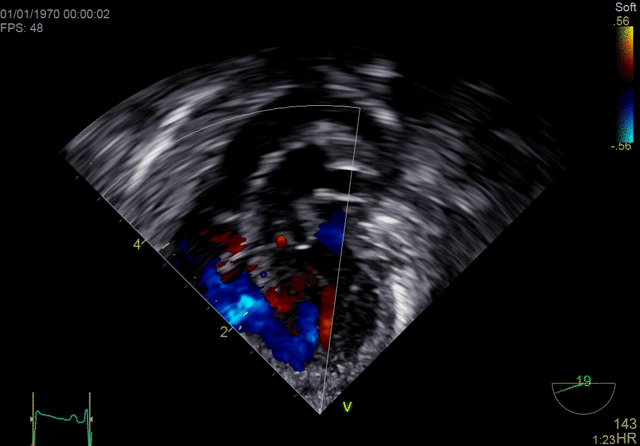

4D color imaging with the 4Vc-D probe

4D TEE color imaging with Vmax